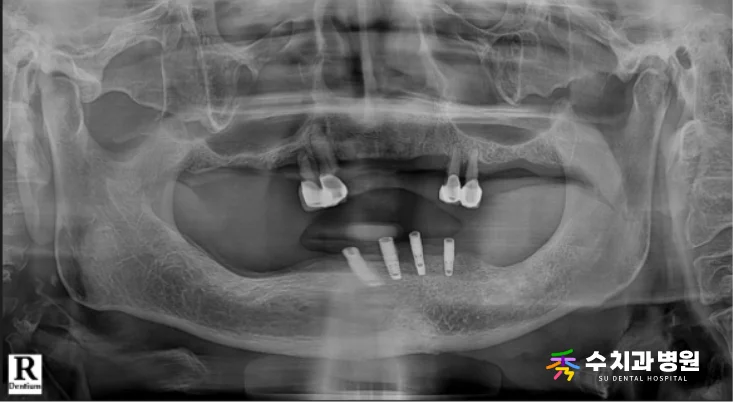

[📸 치료 전 엑스레이사진] (촬영일: 2025년 4월)

검진과 방사선 사진을 꼼꼼히 확인한 결과,

남은 치아들이 지지대 역할을 완전히 상실하여

정상적인 기능 유지가 불가능했습니다.